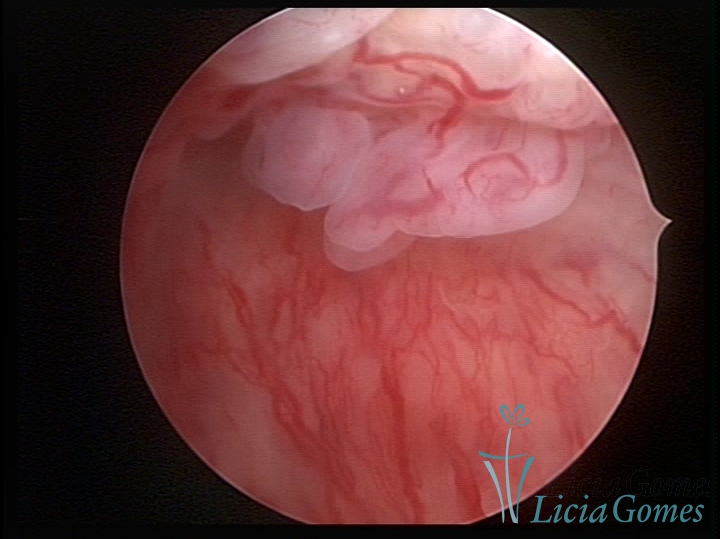

PÓLIPOS ENDOCERVICAIS

São tumores benignos, resultantes da proliferação focal reativa aos processos inflamatórios ou à situações de hiperestrogenismo, e podem ter sésseis (com a base de implantação larga) ou pediculados do epitélio.